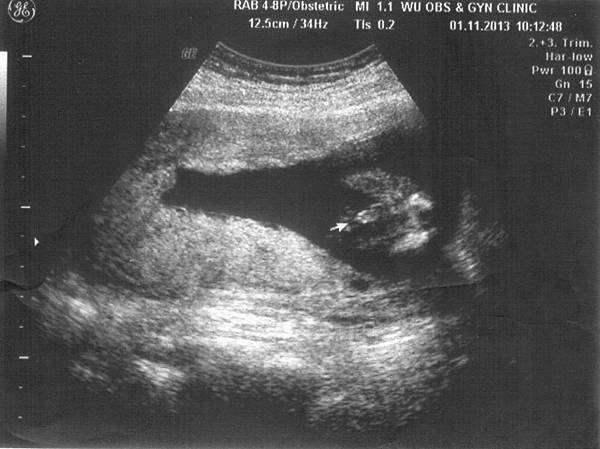

• 10月 10 週四 201319:33

• 暈船中的小小寶貝

12W2D-1.jpg 12W2D-2.jpg

九月去了趟日本玩,回來就被貝拉傳染感冒,到現在都還沒好…

每天都在咳咳咳,中西醫都不敢開重藥,所以得要靠我自己本身的免疫力來打敗感冒,

回娘家休養近兩週,雖然咳嗽有好點,但咳起來還是很可怕,

我總是很害怕會影響肚子裡的小小寶貝啊~

(繼續閱讀...)